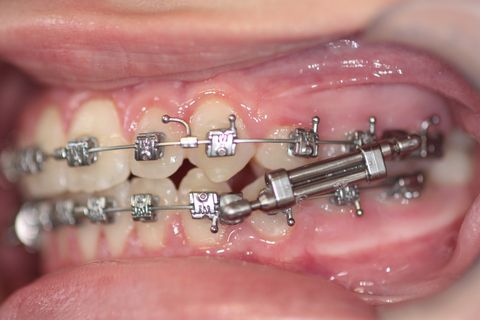

Uso do Twin Force por aproximadamente 3 meses

Twin Force